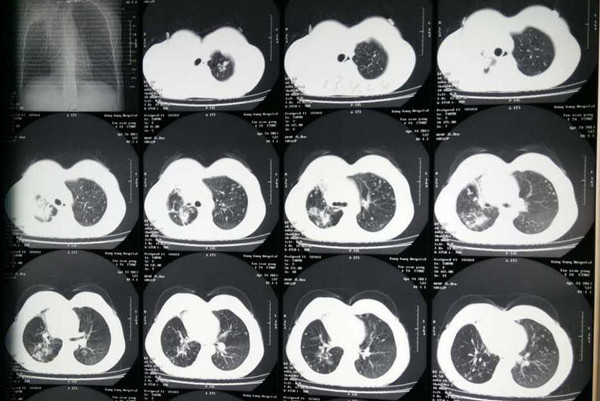

肺结核是一种传染性疾病,治疗一般需要6-9个月,对于出现副反应、耐药可复发等情况,治疗时间会更长,因此,在得了肺结核后一定要选择正确正规的治疗医院,早发现早治疗,并遵循早期、规律、联合、适量、全程的十字方针,坚持用药治疗。那么肺结核治疗有哪些方法呢?